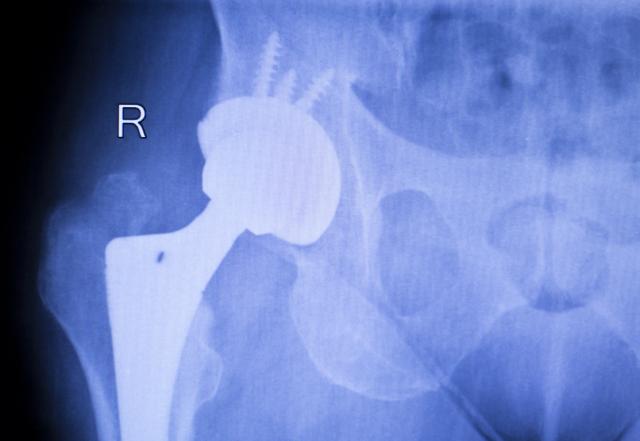

Dr Zoran Baščarević, direktor Instituta "Banjica", za Večernje novosti je rekao da je funkcija veštačkog kuka sada toliko približna funkciji biološkog zgloba da pacijenti posle ugradnje mogu čak i da se bave sportom.